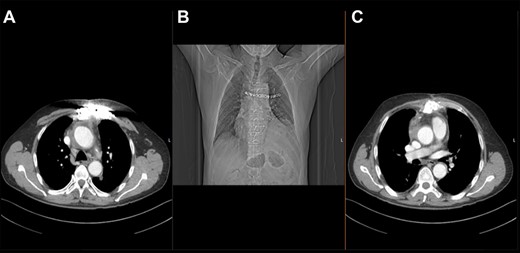

After cardiopulmonary bypass initialization and opening the sternum, one could see the fistula path affecting only the left side of the manubrium sterni and reaching into the mediastinum. Around the ascending aorta was an infected hematoma, with clear infiltration of the Dacron patch, no signs of aortic root abscess or infection. The patient underwent hypothermic circulatory arrest with selective antegrade brain perfusion. The ascending aorta and the proximal two-thirds of the aortic arch were replaced with a cryopreserved aortic homograft (Fig. 2). The fistula path together with the manubrium sterni and the cartilage to the second left rib were completely resected. The rib was then fixated to the right side of the sternum using a titanium plate. The remaining sternum was treated with antiseptic solution and was then conventionally closed with sternal wires. The pectoralis major was mobilized on both sides together with the skin and was used to stabilize the wound.

Intraoperative photograph demonstrating the surgical result after homograft replacement of the ascending aorta and aortic hemiarch.